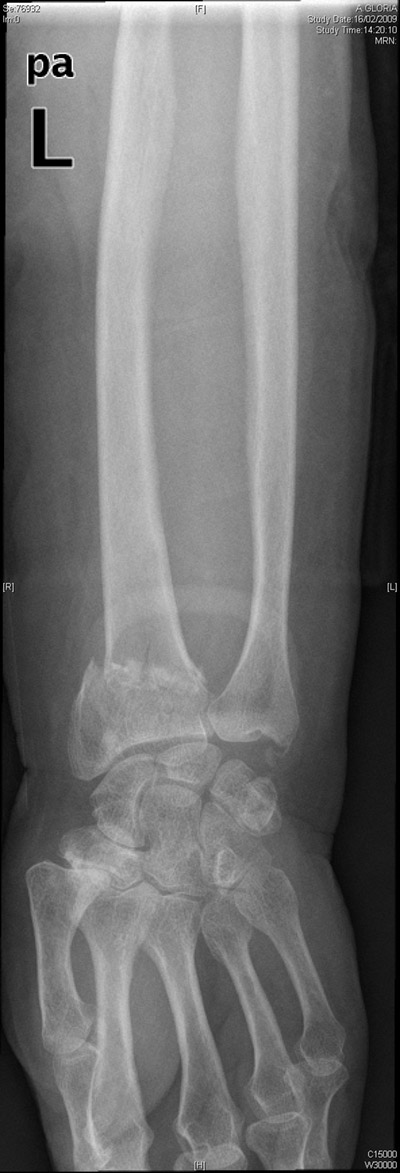

Carpo normal

ACT Alteraciones degenerativas en muñeca.

Fractura de radio.